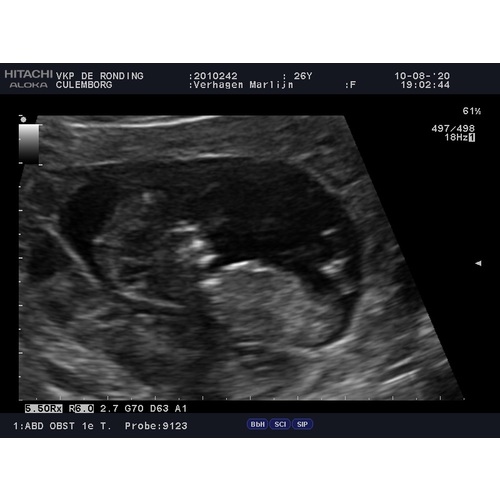

Je kan best al veel zien! Dit waren enkele plaatjes van mijn 12 weken echo. Ik was toen ook exact 12 weken zwanger